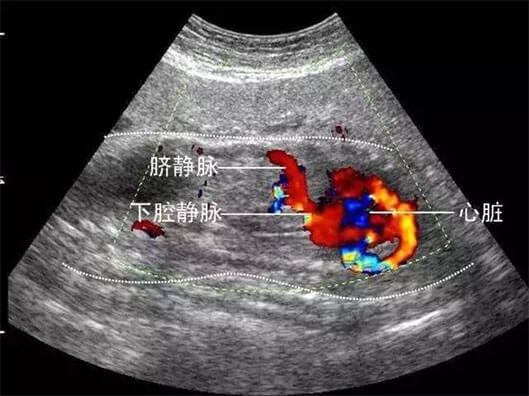

彩超的分辨率一般会比黑白B超高,而且用彩色标注血流,当脐带绕颈的时候就会看见胎儿脖子上呈U形或者W形的血流,对是否脐带绕颈也就一目了然。